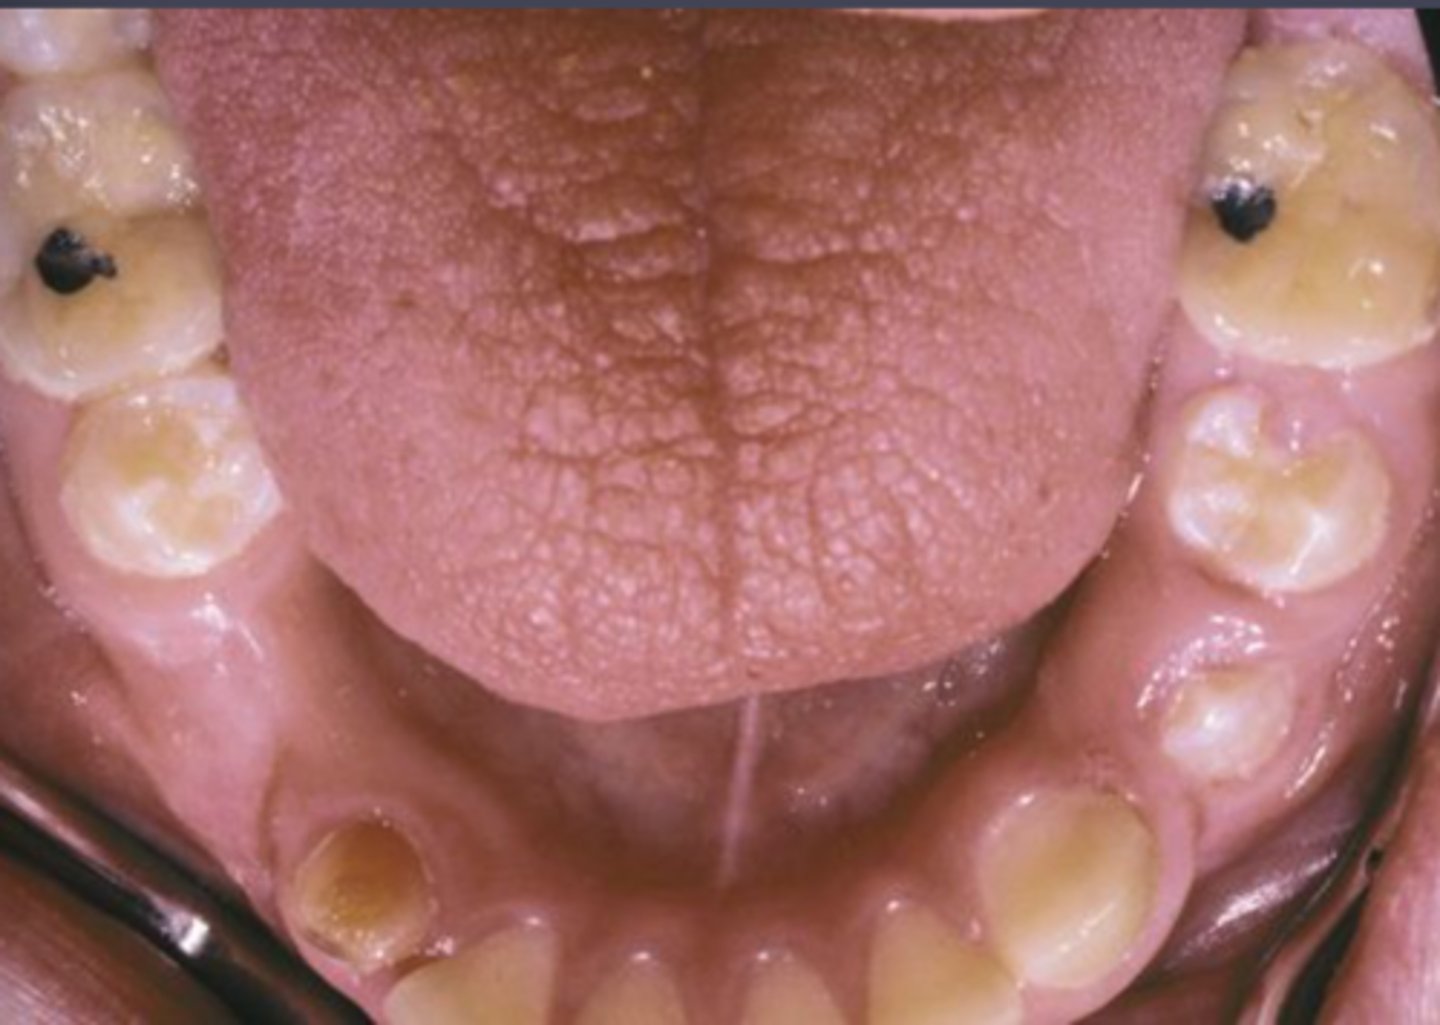

Mucocele

Damage or severing of salivary gland duct, Not a true cyst

what is one of the most common oral ST enlargements?

false ( they do: rupture, drainage,

reforming)

T or F: Mucocele do not fluctuate in size

• Granulation tissue

• Spilled mucin

• Inflamed salivary gland tissue

upper lip

What location is the LEAST common site for mucoceles?

excision, removal of adj salivary gland tissue

What are the treatments for a Mucocele